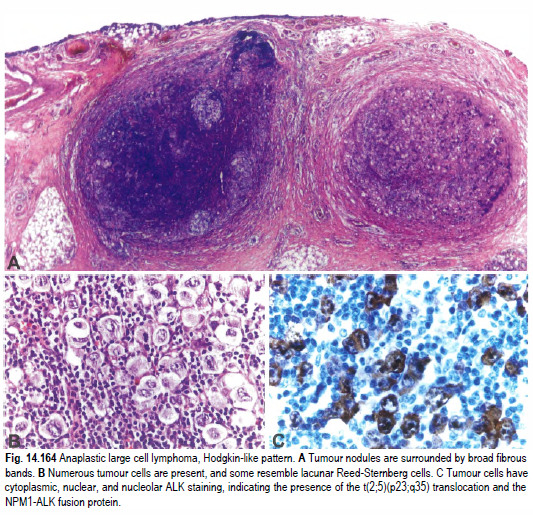

间变性大细胞淋巴瘤,ALK阳性 – 91360智慧病理网

ALK阳性间变性大细胞淋巴瘤 – 慧海拾穗博客 – 华夏病理网博客